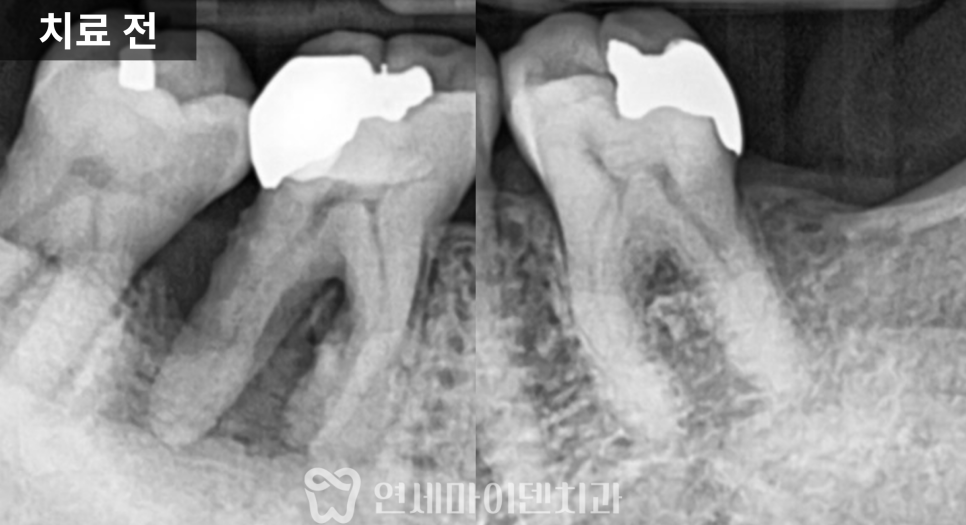

해당 치아는 왼쪽 아래 어금니였고,

잇몸에서 고름이 배출되는 통로가 형성되어 있는 상태였습니다.

엑스레이를 확인해보니

일반적인 포스트가 아니라

캐스트 포스트가 깊게 삽입되어 있었고,

주변 신경치료 상태 역시

깔끔하게 마무리된 형태는 아니었습니다.

이러한 경우에는 단순 치근단 염증뿐 아니라

치근파절 가능성을 반드시 함께 고려해야 합니다.

잇몸 여드름 위치가 의미하는 것

잇몸에는 고름이 배출되는

소위 ‘잇몸 여드름’이 형성되어 있었는데,

그 위치가 치아의 상방 쪽에 자리하고 있었고

뿌리를 따라 세로 방향으로 뼈가 녹아 있는 양상이 관찰되었습니다.

이런 형태는 일반적인 염증보다

치근파절에서 자주 보이는 패턴으로,

겉으로는 단순 염증처럼 보여도

내부 구조적인 문제가 있을 가능성이 높은 상태였습니다.